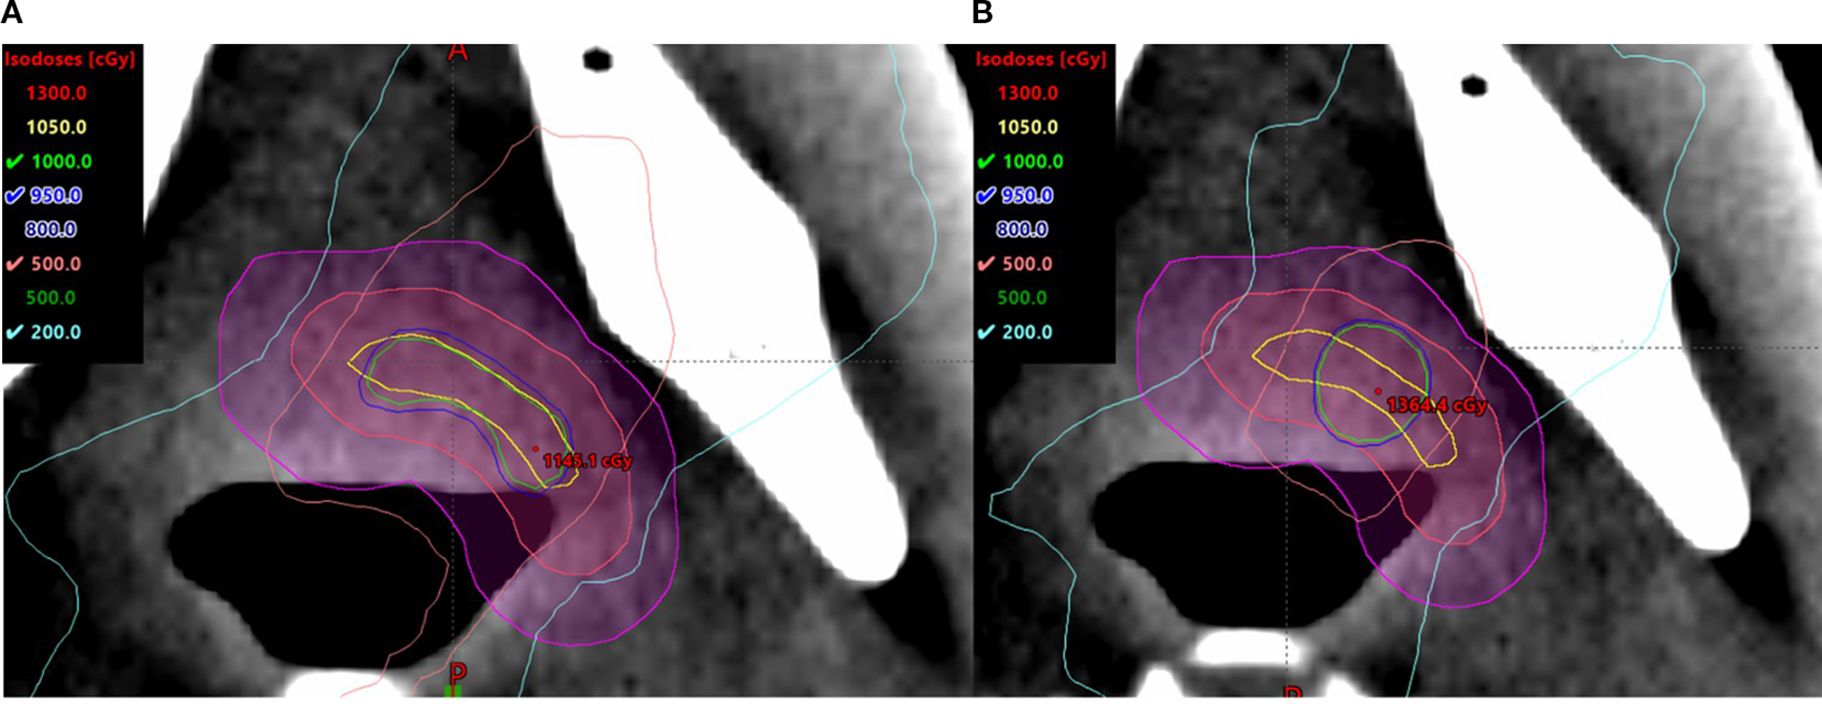

The small, irregularly shaped targets are found to be prone to being affected by the size and location of the high-dose cores. Compared to the spherical V_SHDCx, the plans with irregularly shaped targets demonstrated greater EUDs (Table 2) when using a conformal structure (V_cSHDCx). However, the plans using conformal high-dose core structures required more dose modulation, resulting in approximately 30% more monitor units compared to the plans using spherical high-dose cores. This means that higher EUDs were delivered at the cost of a 30% longer running time. As shown in Figure 6, there was more dose spillage in the periphery and outside the GTV. Therefore, plans using spherical V_SHDC demonstrated better VGTVp<3Gy compared to those using irregularly shaped V_cSHDC (Table 2).

Figure 6. Irregularly shaped target using V_cSHDC (A) and spherical V_SHDC of an equivalent volume (B).